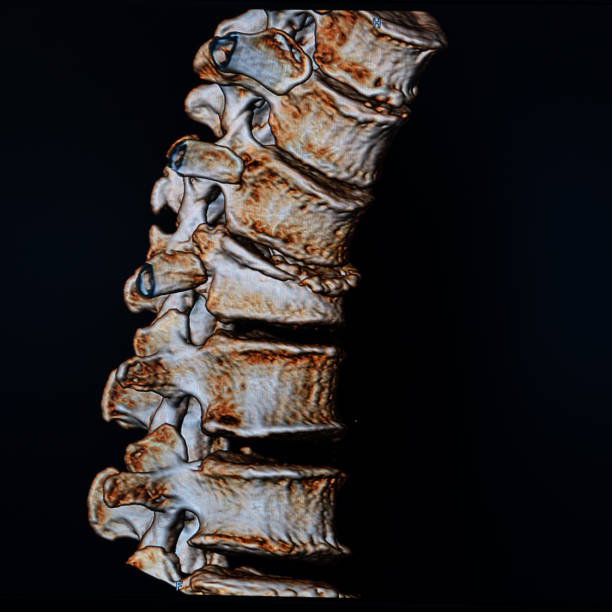

골반은 복부 하단에 위치하고 있는데 양쪽의 2개 볼기뼈와 후단부의 천골(엉치뼈)와 미골(꼬리뼈)로 구성되어 있으며 척추 부분과 하지를 연결하여 체중을 지탱하며 각종 내장과 자궁, 난소, 방광 등 주요 장기를 외부 충격에서 보호할 수 있습니다.